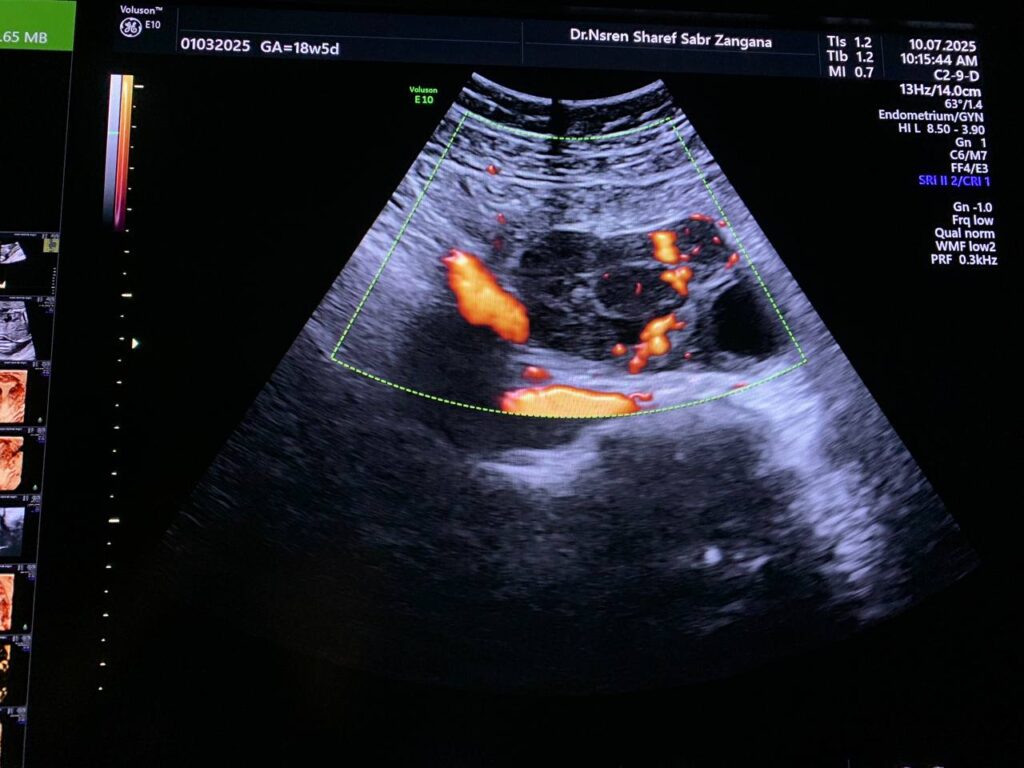

Pelvic Ultrasound

· Bulky size uterus, endometrial lining thickness 13mm, clear endo-myometrial junctional zone, the myometrial layer is heterogenous in texture, no fibroid

· Left ovarian solid mass vascular on color doppler score 2-3 , its size 57x48mm, no ascites , no enlarged lymph node seen, picture mostly ovarian tumor , please for further study.